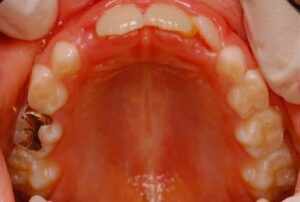

歯に詰めるプラスチックが危ない パート2

1月15日に、奥歯に詰めたプラスチックの周りから虫歯になっている人が非常に多いという話をしました。 今日もそんな患者様がいらっしゃいました。下の写真です。 麻酔をして、プラスチックを外すと、前回のように虫歯が拡がってボロボロというほどではな […] 本文を読む

歯に詰めるプラスチックが危ない

今、歯に詰めたプラスチックの周りから虫歯になっている人が非常に多いです。特に奥歯に詰めた咬み合わせの面のプラスチックが非常に危険です。 どうして、こんな事が起こるのかと言うと、最大の原因は、プラスチックが硬化する時の収縮です。 虫歯の治療は […] 本文を読む